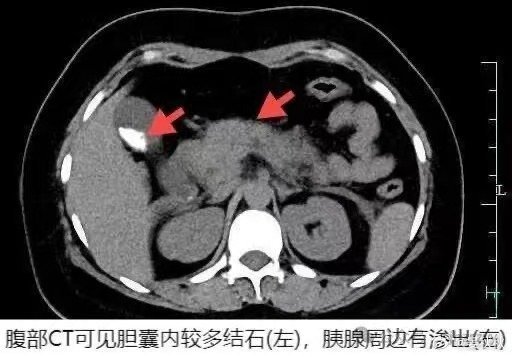

杭州25岁的姑娘小慧,查出胆囊结石,没放在心上。这一天,父母在家中准备了清蒸大螃蟹,小慧一连干掉了四只。饭后不久,她突然感到上腹部隐隐作痛,以为只是吃多了忍忍就好,但半个多小时后疼痛加剧,家人立即将她送往杭州市中医院急诊。

结果,医生诊断她正是因为进食大量螃蟹,而引起了急性胰腺炎,需要马上住院。最终医生给她做了胆囊切除手术。